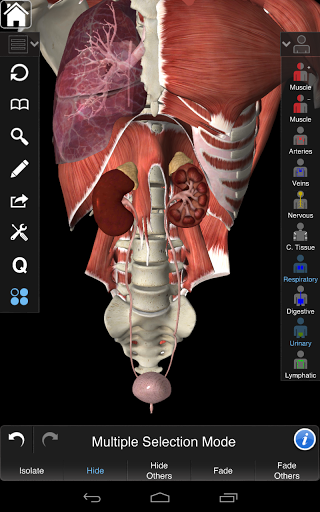

Essential Anatomy 3 es receptivo, visualmente impactante y sin esfuerzo. La aplicación es totalmente en 3D, lo que significa que puedes ver cualquier estructura anatómica de forma aislada y desde cualquier ángulo.

La funcionalidad inteligente que se encuentra dentro de la aplicación permite al usuario eliminar capas de músculo a través de la herramienta 'bisturí'. Esta aplicación ofrece a los usuarios la posibilidad de activar / desactivar sistemas sin la necesidad de anular la selección de estructuras individuales o mezclarse en una multitud de pestañas regionales predefinidas, como otras aplicaciones.

Essential Anatomy 3 está diseñado pensando en el usuario: el cuerpo mismo se convierte en la interfaz. A diferencia de otras aplicaciones 3D, que se basan en arreglos anatómicos predefinidos y disecciones regionales para guiar al usuario, Essential Anatomy 3 de 3D4Medical le permite encontrar lo que está buscando sin complicaciones.

---- Modo de selección múltiple - Ocultar / Fundir / Aislar estructuras individuales o múltiples

---- Interfaz intuitiva y fácil de usar